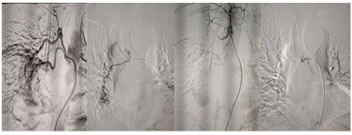

Figure 2:

CASE 2: Left bronchial artery embolisation in a case of bronchiectasis. A-Hypertrophied bronchial artery with significant blush in left lower lobe. B-The magnified view of blush in left lower lobe. C-Post embolisation with PVA particles with patent stump.